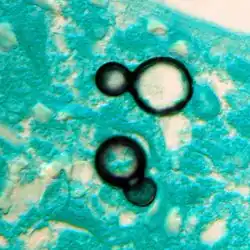

Once suspected, the diagnosis of blastomycosis can usually be confirmed by demonstration of the characteristic broad-based budding organisms in sputum or tissues by KOH prep, cytology, or histology.[27] Tissue biopsy of the skin or other organs may be required to diagnose extra-pulmonary disease. Blastomycosis is histologically associated with granulomatous nodules.

Granuloma with early suppuration. The fungal organisms are difficult to recognize at this low magnification. -

Large yeast-like fungi seen within giant cells at arrows. -

Large yeast-like fungi seen within giant cells at arrows. Budding yeasts in the cytoplasm of giant cells at the arrows. Broad-based budding and double-contoured cell walls are seen in the giant cell in the center are characteristic of Blastomyces dermatitidis. -